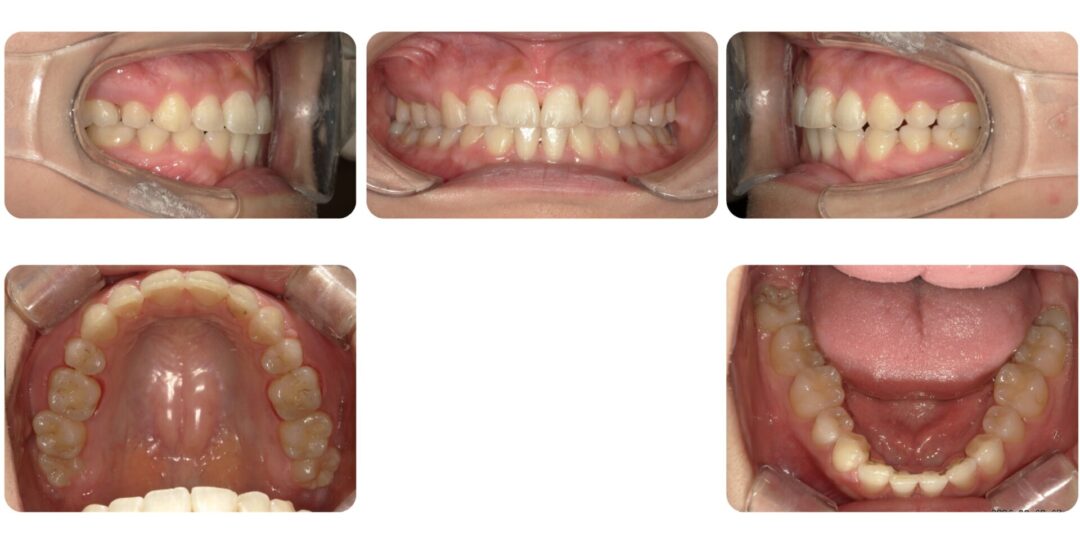

下顎左右犬歯先天性欠如を伴う叢生|初診時24歳

矯正治療前

上の前歯が片方前に出ている

治療内容

成人歯科矯正 上顎左右第一小臼歯抜歯 マルチブラケット装置

治療期間

3年4ヶ月